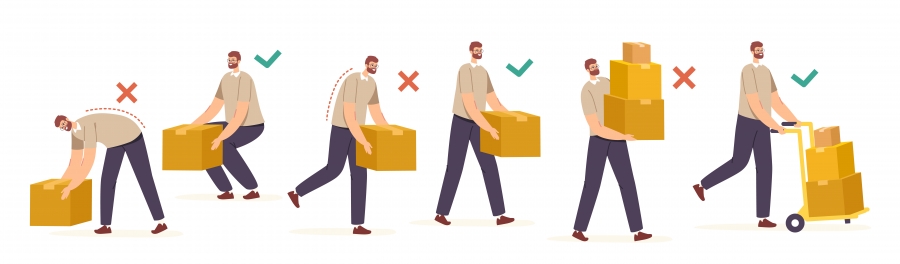

Nepravilno dvigovanje težkih predmetov

Če težki predmet dvignete na način, da vso silo usmerite v hrbtenico namesto v noge, imate večjo možnost za nastanek hernije diska. Zakaj?

Ko dvignete npr. težko škatlo z usločeno hrbtenico, se medvretenčni prostori povečajo in disk zlahka “pade” iz medvretenčnega prostora ter začne pritiskati na hrbtenjačo. V primeru pravilnega dviga je hrbtenica vzravnana in vso težo, ki jo morate dvigniti, usmerite v noge.